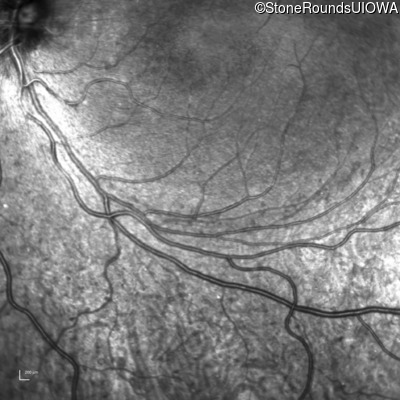

Infrared Fundus Photograph - Right - 20/25 -1

Exemplar